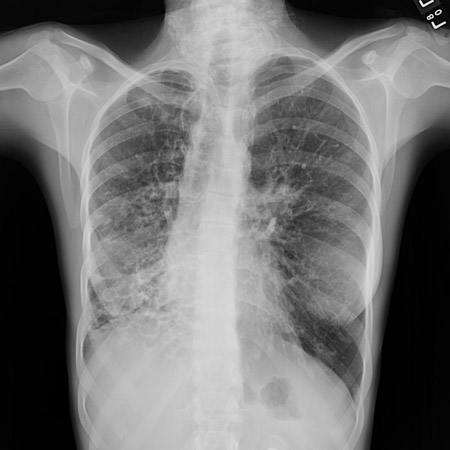

Chest x-ray of acute pulmonary edema showing increased alveolar markings, fluid in the horizontal fissure, and blunting of the costophrenic angles

From the private collections of Syed W. Yusuf, MBBS, MRCPI, and Daniel Lenihan, MD